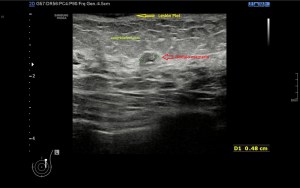

4

En la imagen 4 aparecen los calcios lineales, típicos de las entensopatías de inserción y que también fluctuarán según el grado de afectación locorregional.

Ambas apariencias de las calcificaciones suelen verse acompañadas de tendinopatías, como muy puedes ver en la imagen 8 donde se demuestra un aumento del vientre del tendón marcado por la línea rosa, y como hemos dicho anteriormente, comos a unos 5 cms de la inserción.